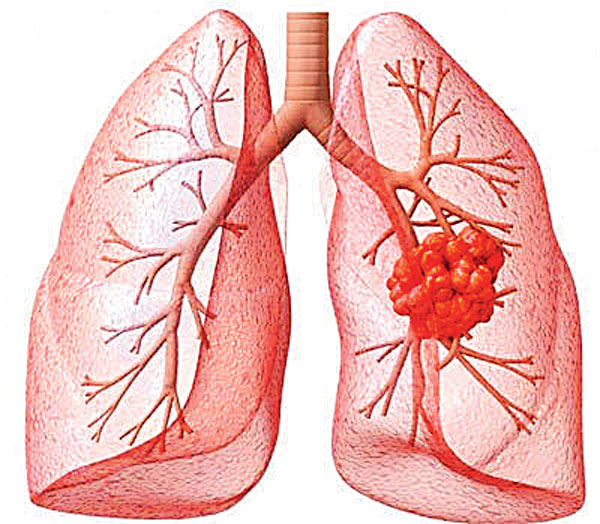

ফুসফুসের ক্যানসারের ঝুঁকি আছে কি? চিনিয়ে দেবে পাঁচটি লক্ষণ

ফুসফুসের কোন সঙ্কেত বলে দেবে বিপদ বাড়ছে? কী দেখলে সতর্ক হওয়া প্রয়োজন

নাগাড়ে কাশি, স্বরে বদল ফুসফুস ক্যানসারের উপসর্গ হতে পারে

ফুসফুসে ক্যানসার রুখতে চাই সতর্কতা